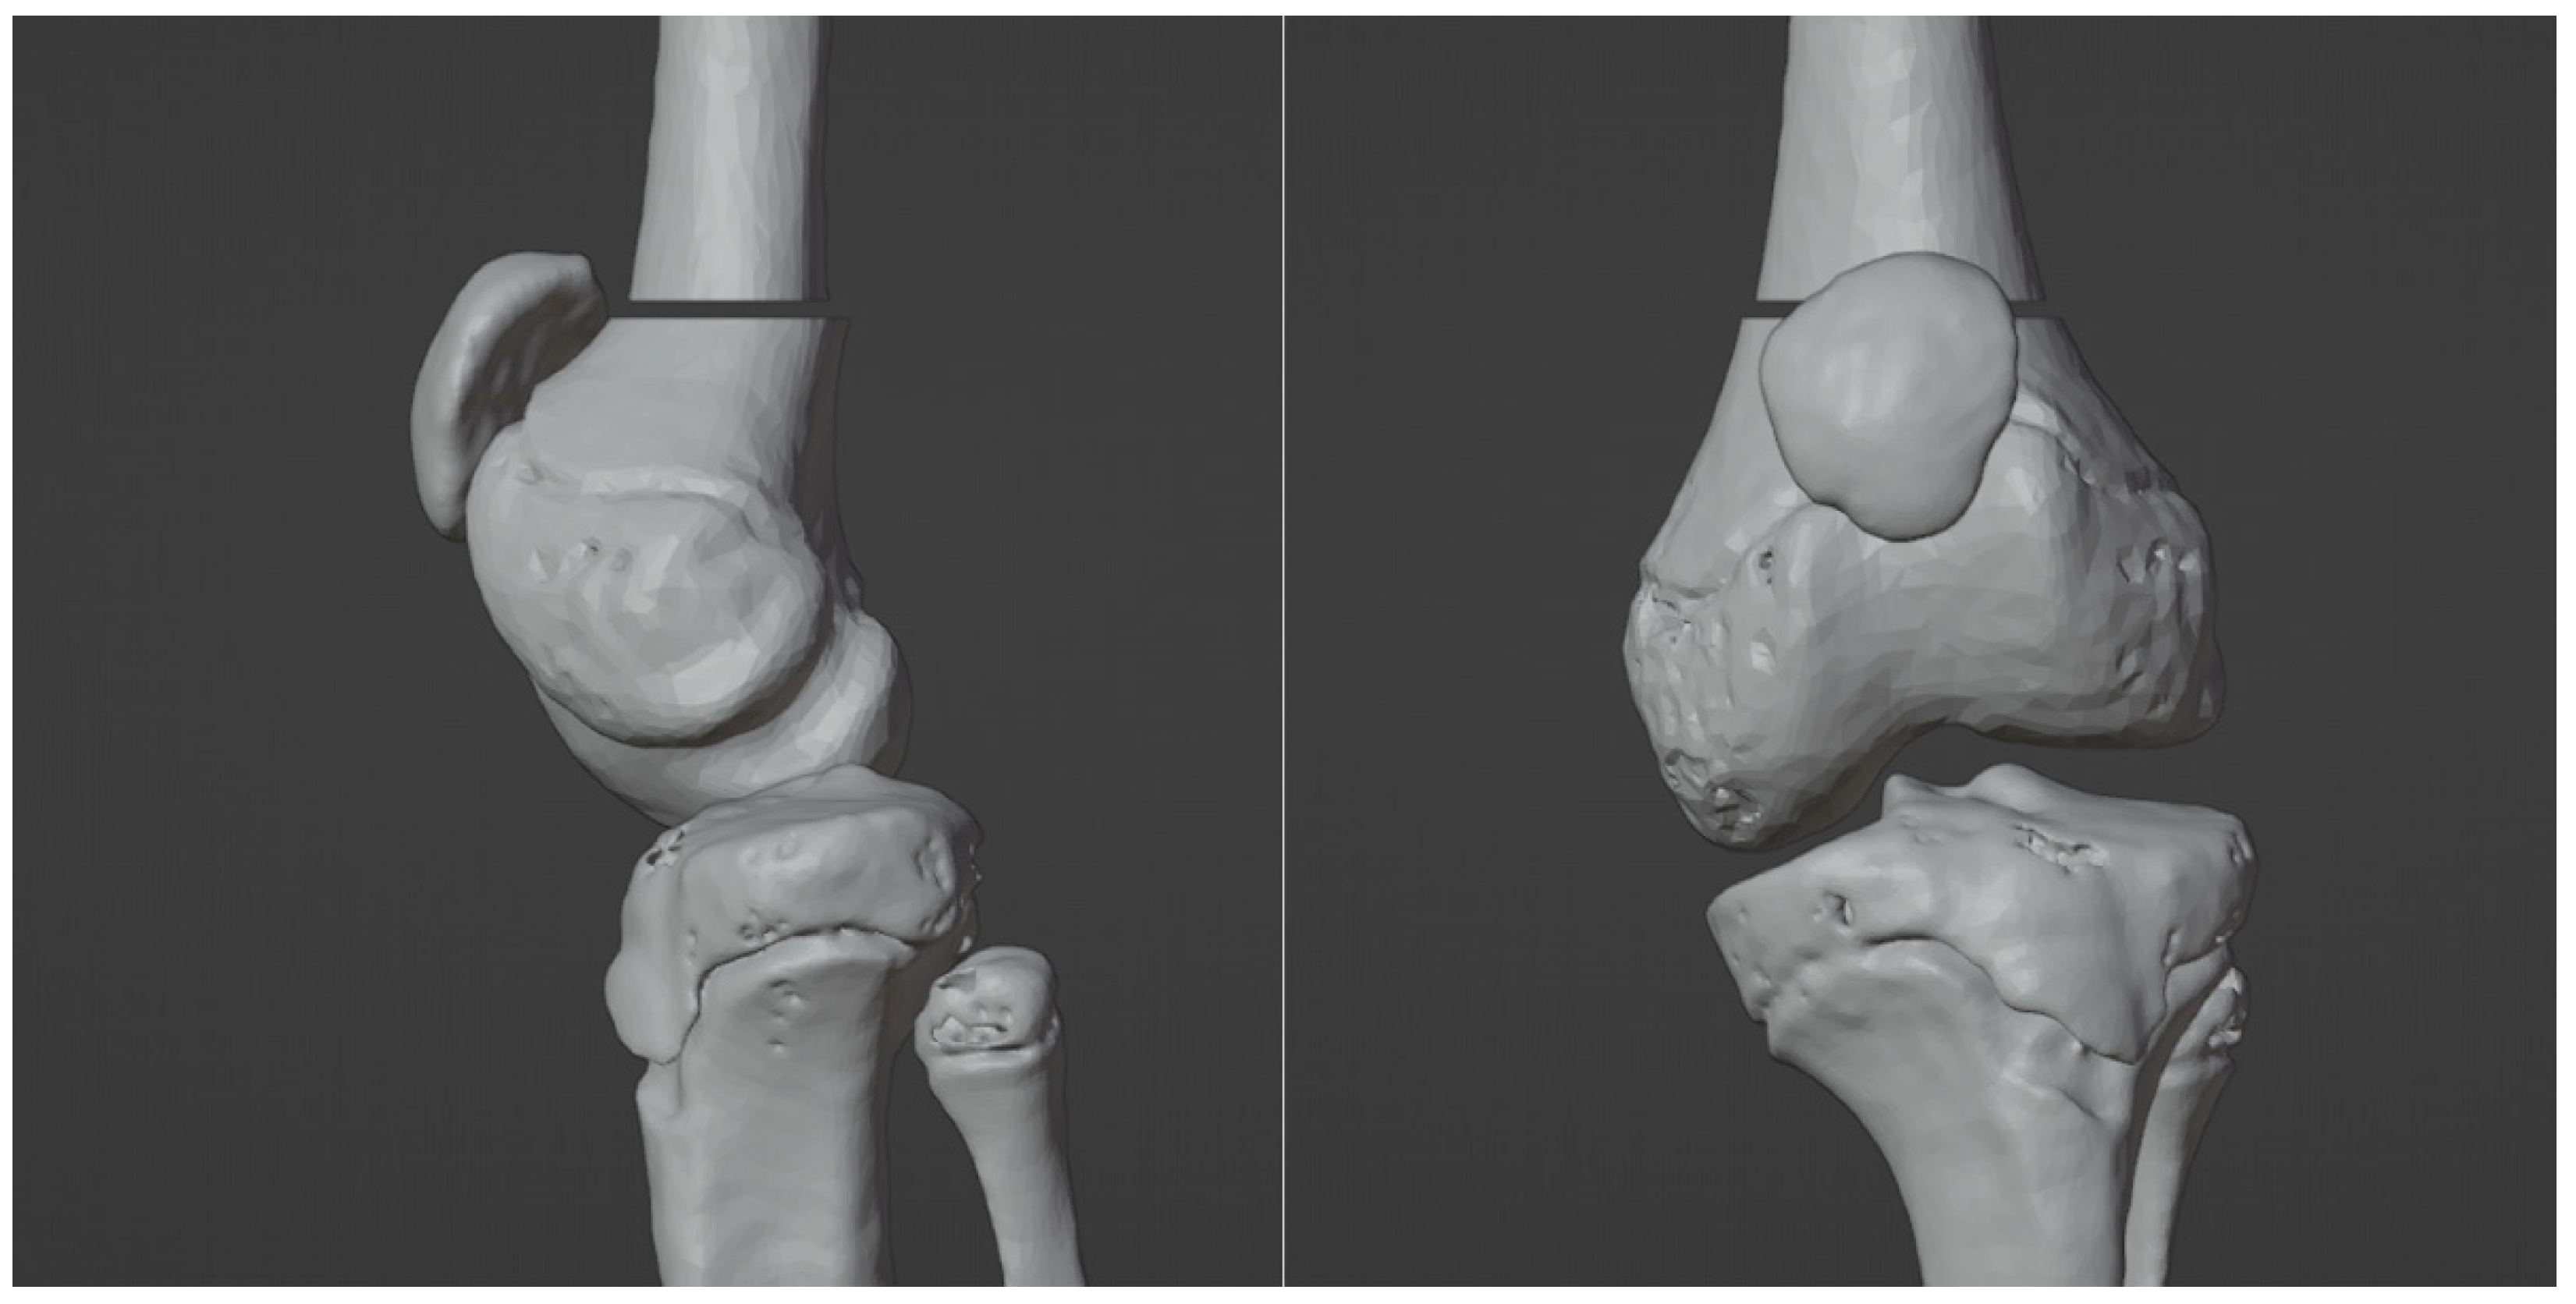

3.4. Virtual Surgical Simulation